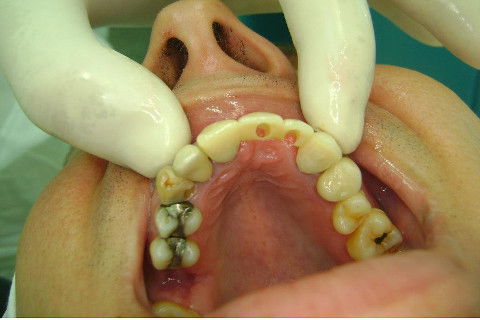

Paciente apareceu em meu consultório em dezembro/2013 para resolver problema de insatisfação com ponte fixa provisória anterior, realizada há 9 anos atrás (2004)...pretendia realizar somente a reabilitação em maxila/anterior, não contava com outros problemas com maior gravidade na sua boca, o máximo que citou foi a indicação para a exodontia do 16...

Cirurgia realizada hoje de manhã...No planejamento percebi medindo espessura do rebordo com especímetro que as medidas não estavam muito boas, ou o ideal, em torno de 4,5 a 5 mm ate´o terço médio do rebordo e melhorava no final, com 6 a 7 mm. Optei então por uma pequena expansão usando os expansores rosqueáveis. Aconteceu uma pequena fenestração na hora da fixação dos implantes, especialmente na região do 22 que fraturou o início da tábua óssea, mas não me preocupei porque não foi mais do que 2 mm de fratura em direção apical, o implante ficou infraósseo e com boa estabilidade (60 N no 21 e 40 N no 22). Esta fratura tb não deixou osso completamente solto, foi do tipo galho verde, deixei em posição e suturei normalmente. Só não fiz e nem estava planejado carga imediata mesmo, mais pelo motivo da oclusão inadequada do caso.